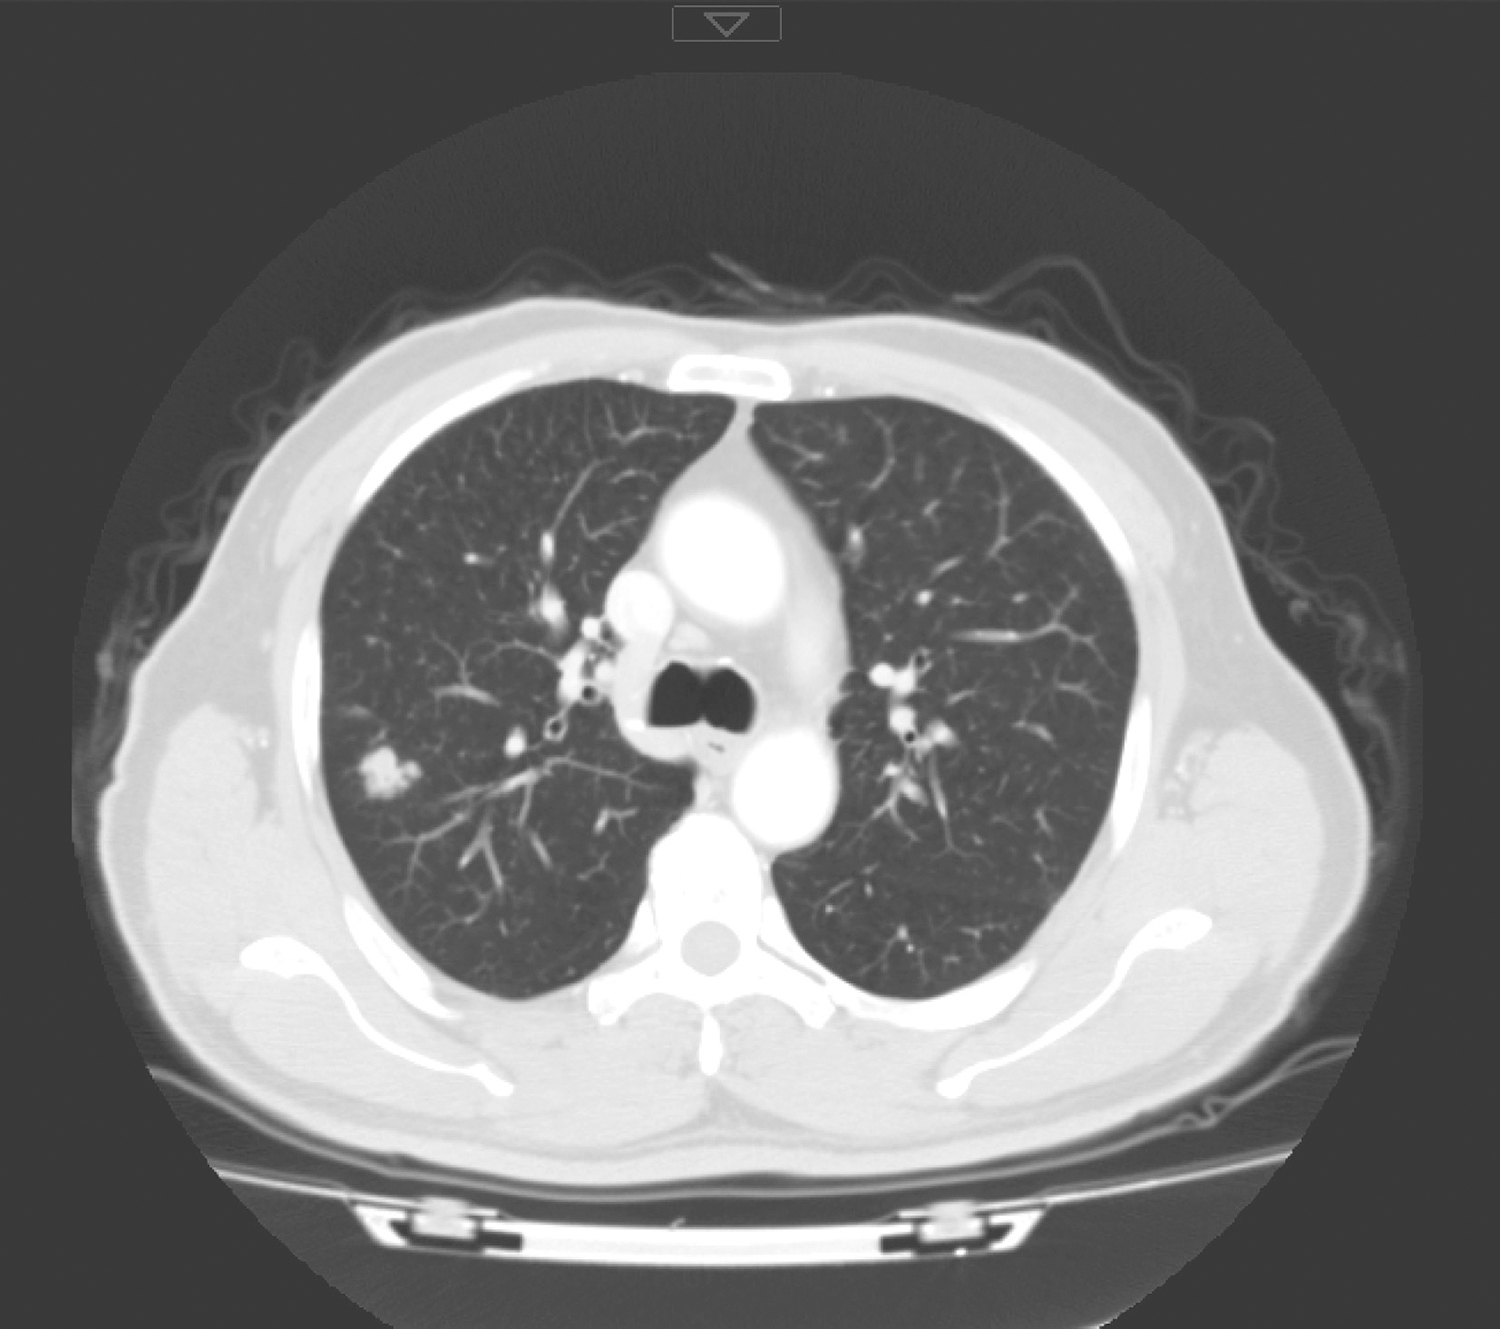

3.2016年11月28日颈胸部CT

检查所见:会厌根部局部略不均匀,舌根部见结节样不均匀强化,余咽喉未见明确肿物。双颈未见明确肿大淋巴结。右肺上叶后段结节,最大截面约1.4cm×1.0cm,边界尚清,边缘见少许毛刺及条索,周边见多个小结节(图2)。余肺未见明确结节或肿物。纵隔及肺门未见明确肿大淋巴结。未见胸腔积液、心包积液。

图2 右肺上叶后段结节

影像学诊断:

(1)会厌根部局部略不均匀,请结合镜检。

(2)舌根部结节样不均匀强化,滤泡增生?请结合临床检查。

(3)右肺上叶后段病灶,考虑结核较肿瘤可能大,请结合临床。